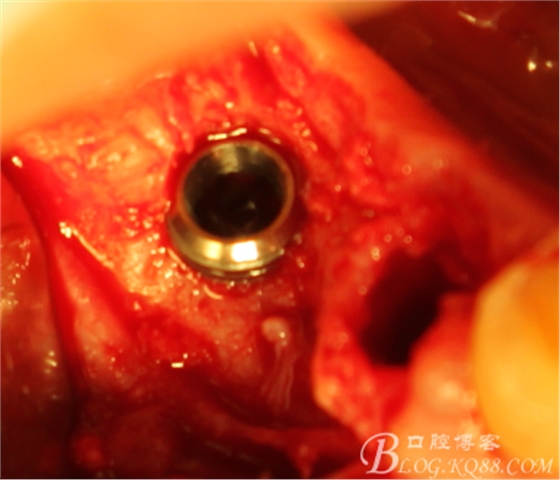

植入植體

C6頰側(cè)填入自體骨,嚴(yán)密縫合關(guān)閉創(chuàng)口

三維檢查種植體位置,方向,平行度